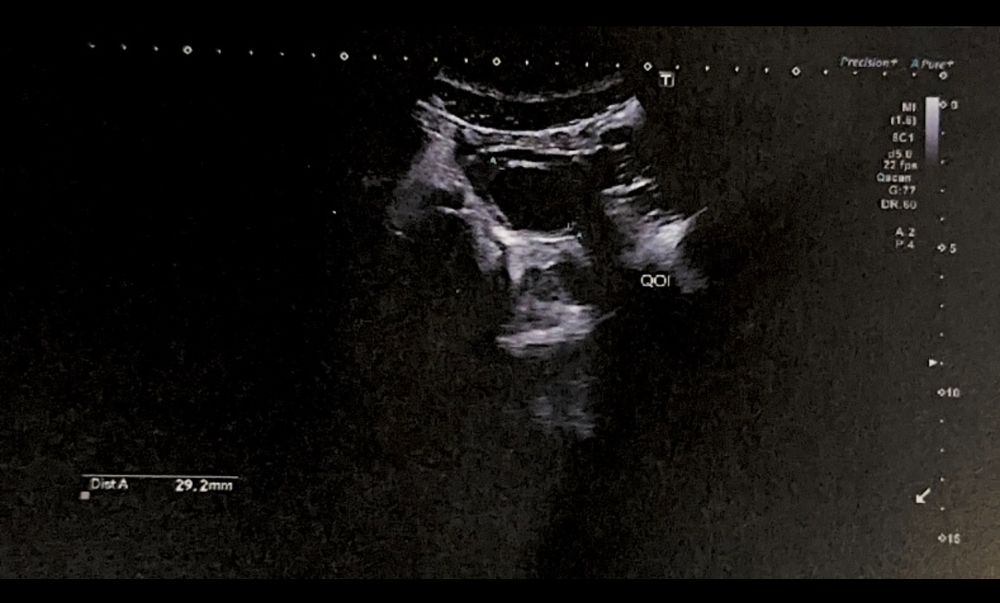

тесты пустые, я уже не надеюсь, думаю, что гормональный сбой, симптомов нет от слова совсем , но и пмс нет 🤷🏼♀️ знаю про позднюю овуляцию, кисты или наоборот надумывание признаков, и т.д)